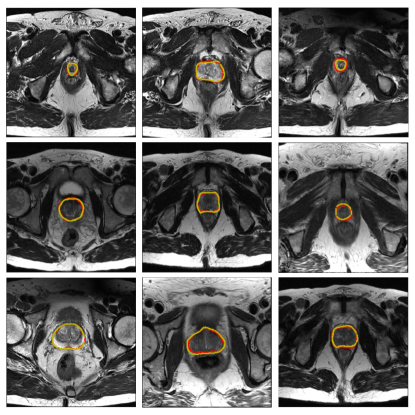

Refer to caption

Figure 4: Sample segmentation results of the prostate. The yellow and red contours indicate ground truth and our segmentation results, respectively.

The results of our proposed BOWDA-Net and the competitors are shown in Table I. Note that all the results reported in this section were obtained directly from the challenge website222https://promise12.grand-challenge.org/evaluation/results/ on Jan 21, 2019. Since there are a large number of team submissions, only evaluation scores of the top 10 teams are listed. As it can be seen from Table I, we performed the best and therefore ranked the first place among all the teams with the overall score of 89.59, which demonstrates the advantage of boundary-weighted knowledge transfer and BWSL. Remarkably, the source domain data utilized in BOWDA-Net is not resampled to match the target domain data, which shows that BOWDA-Net can take general similar data to be easily extended to other medical image analysis tasks, especially those with limited training data. Some qualitative results of our method are shown in Fig. 4. It is observed that BOWDA-Net can produce accurate segmentation results and delineate the clear contours of prostates in MR images.